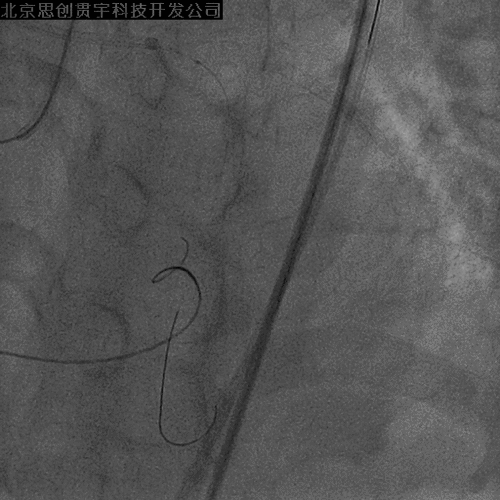

左冠PCI

Culotte技术

LAD—Resolute 3.0*30mm

LM-LCX—Resolute 3.0*30mm

LM-LAD—+Resolute 3.5*30mm

球囊对吻、后扩张

POT